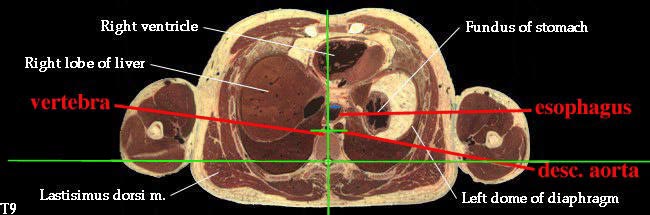

Dissector Answers - Posterior Mediastinum |

1. Define the boundaries of the posterior mediastinum. (W&B 370-371, N231, TG4-14)2. Describe the major contents of the posterior mediastinum and their relationships. (W&B 370, 408-416, N172, N192, N193, N194, N206, N207, N212, N232, N237, N238, N240, N260, TG4-35, TG4-35, TG4-36, TG4-36, TG4-37, TG4-37)

- Descending aorta (thoracic portion): the continuation of the arch of the aorta, supplying oxygenated blood to thorax (except the heart), abdomen, pelvic region, and lower extremities. It begins on the left side, but moves to the midline (to lie on vertebrae) as it descends. The branches of the thoracic descending aorta include:

- Esophagus: enters the mediastinum a little to the right of the median plane, posterior to the trachea. It passes to the middle of the body, then to the left and anteriorly as it travels down to the stomach. (See "Extra Explanation" below.)

3. Describe the organization of the thoracic sympathetic trunk, in addition to its visceral and splanchnic branches. (W&B 413-416, N158, N160, N165, N209, N240, N254, TG4-45, TG4-46, TG8-03, TG8-14)This set of cross-sections might help (no guarantee!):